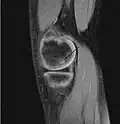

Magnetic resonance imaging (MRI) is useful for staging OCD lesions, evaluating the integrity of the joint surface, and distinguishing normal variants of bone formation from OCD by showing bone and cartilage edema in the area of the irregularity. MRI provides information regarding features of the articular cartilage and bone under the cartilage, including edema, fractures, fluid interfaces, articular surface integrity, and fragment displacement.[37][38] A low T1 and high T2 signal at the fragment interface is seen in active lesions. This indicates an unstable lesion or recent microfractures.[30] While MRI and arthroscopy have a close correlation, X-ray films tend to be less inductive of similar MRI results.[38]